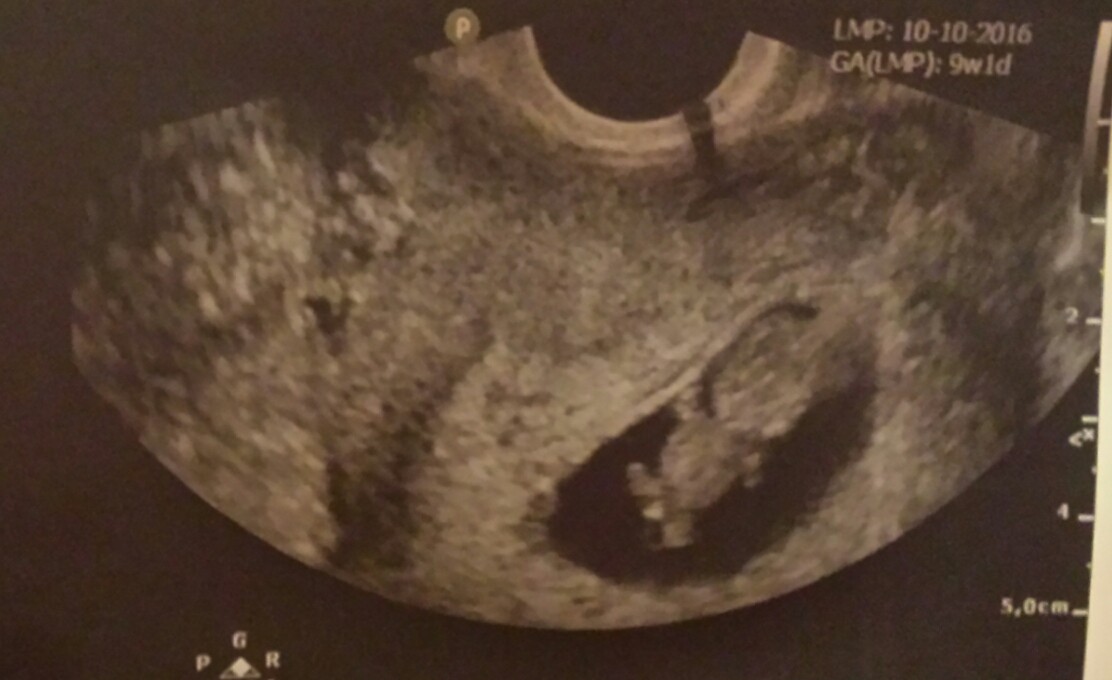

9 tydzien i juz taki widok....niewiarygodne :)

98 KB · Wyświetleń: 437

Jakos faktycznie czuje chlopca, ale jeszcze plci nie moze byc widac. A takiego zdjecia w tak wczesnych etapach sie nie spodziewalan :)

Ja zaczęłam 9 tydzień i dzisiaj miałam wykonane pierwsze USG jestem szczęśliwa staraliśmy się z mężem 10 lat jeździliśmy po klinikach a tu taki cud ... grudzień okazał się magicznym miesiącem , straciłam nadzieje już dawno,dzięki miłości męża i wsparciu rodziny zawsze jakoś funkcjonowałam ale teraz czuje ze żyje na nowo [emoji16] pozdrawiam dziewczyny życzę dużo zdróweczka [emoji122]